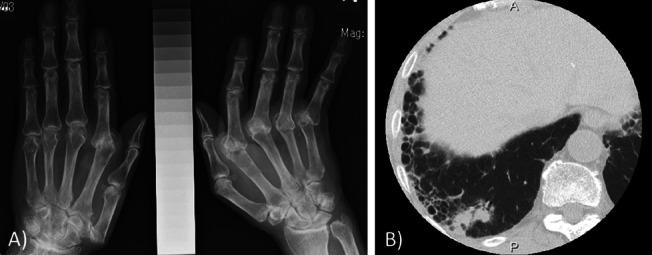

An elderly patient with long-standing RA was admitted to our hospital with acute respiratory failure. Computed tomography upon admission showed diffuse ground-glass opacities superimposed with subpleural reticular shadowing and honeycombing and multiple nodules in the lungs and liver. Despite the discontinuation of MTX and introduction of an immunosuppressive regimen with pulse methylprednisolone followed by a tapering dose of prednisolone and intravenous cyclophosphamide, the patient died due to the acute exacerbation (AE) of RA-related interstitial lung disease (ILD) following the parallel waxing and waning of a diffuse interstitial shadow and pulmonary and liver nodules. At autopsy, RNs were scattered throughout both lung fields in addition to extensive interstitial changes. RNs were also detected in the liver and kidneys. The foci of cryptococcosis were mainly identified in alveolar spaces. Based on the clinical and pathological findings, these nodules were most consistent with ARN because of acute increases in the size and number of previously detected pulmonary nodules.

一位患有长期 RA 的老年患者因急性呼吸衰竭而入院。入院时的计算机断层扫描显示弥漫性磨玻璃影伴胸膜下网状影和蜂巢影,肺部和肝脏有多发性结节。尽管停用了 MTX,并采用脉冲甲基强的松龙联合逐渐减量的泼尼松龙和静脉环磷酰胺的免疫抑制方案治疗,但由于 RA 相关间质性肺病(ILD)的急性加重(AE),患者最终死亡,ILD 的表现为弥漫性间质影以及肺部和肝脏结节的平行消长。尸检时,除了广泛的间质改变外,双肺野还散布着 RNs。肝脏和肾脏也发现了 RNs。隐球菌病的病灶主要位于肺泡腔。基于临床和病理发现,这些结节最符合 ARN,因为先前发现的肺部结节的大小和数量急性增加。